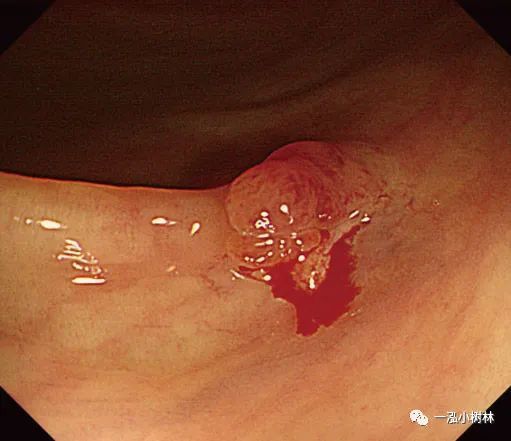

图5f 息肉取出后出血

图5g 黏膜出血止血